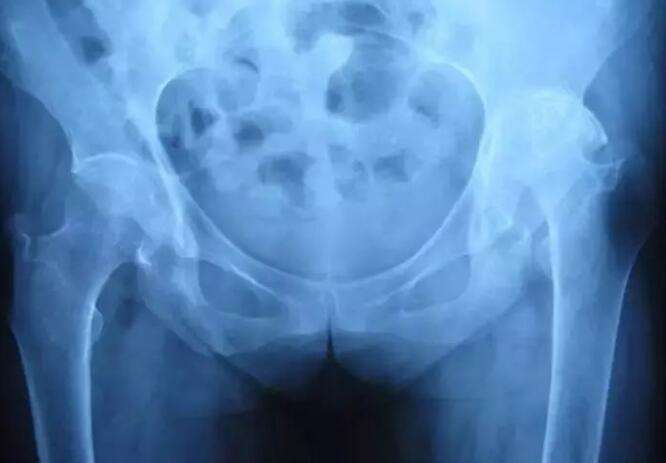

强直性脊柱炎是一种慢性炎症性自身免疫性疾病,主要涉及脊柱和骶髂关节。所谓的强直意味着僵硬和强迫直立。主要指颈椎,腰椎不能移动。简言之,头部不能左右旋转,点头等,不能弯腰等。强直性脊柱炎是一种慢性进行性疾病。早期患者常表现为背痛、晨僵、胸痛和外周关节疼痛。随着疾病的发展,后期主要表现为中轴关节和外周受累关节的畸形骨性强直,关节失去活动性,患者的自理能力、社会适应能力和就业受到不同程度的影响。具有慢性、进行性等特点,使病程延续一生。当它发生时,患者无法忍受疼痛并遭受痛苦。因此,它被称为不死癌症。

强直的诊断可以遵循规则,更容易诊断,也不容易误诊或遗漏诊断。许多网民知道这种疾病后,一旦有背痛,他们就会想到这种绝症。脊柱、颈椎、尾椎等部位的病变较多,背痛的原因较多,最常见的是椎间盘突出症。但如果强直患者能及时诊断和合理治疗,他们就能控制症状,改善预后。通过非药物、药物、手术等综合治疗,缓解疼痛和僵硬,控制或减少炎症,保持良好的姿势,防止脊柱或关节变形,必要时纠正畸形关节,以提高患者的生活质量。